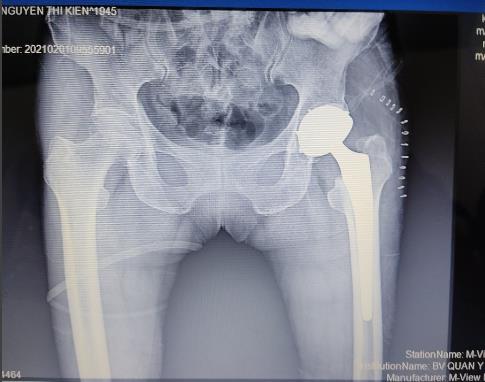

Gãy cổ xương đùi di lệch Thay khớp háng toàn phần điều trị gãy cổ xương đùi di lệch

- Chấn thương khớp háng: gãy cổ xương đùi di lệch ở bệnh nhân cao tuổi; gãy nhiều mảnh chỏm xương đùi; gãy liên mấu chuyển mất vững ở bệnh nhân cao tuổi, loãng xương nặng mà trước đó chức năng khớp còn tốt.